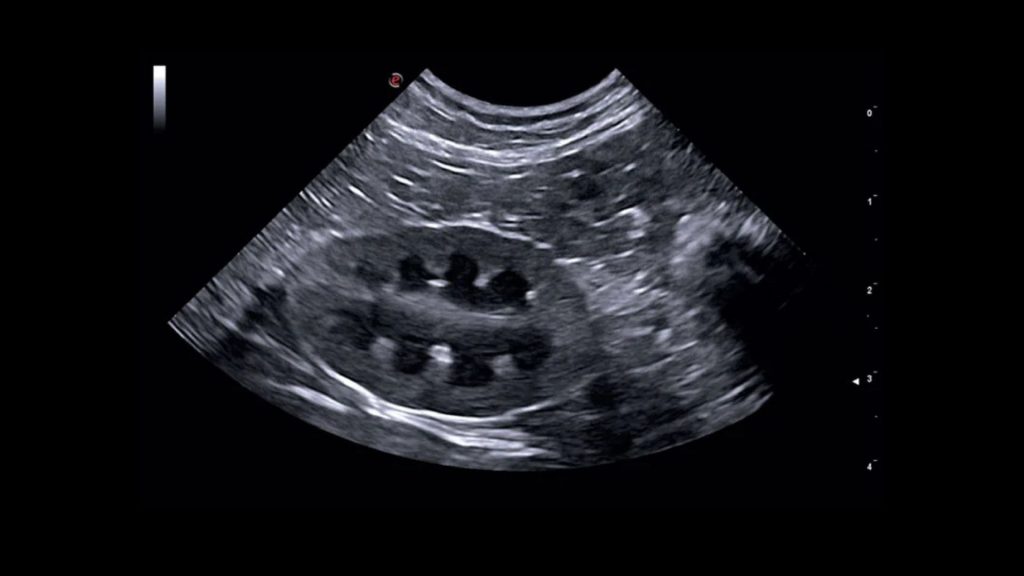

Ultrasonlar genellikle evcil hayvan masanın üzerinde yatarken yapılır. Veteriner hekimi karın derisine bir prob tutar. Prob cilt üzerinde hareket ettirildiğinde içerideki yapılara ses dalgaları gönderir ve daha sonra ekranda siyah beyaz gerçek zamanlı görüntülere dönüştürülür. Tüyler ses dalgalarının iletimini sekteye uğratacağı için evcil hayvanın karnı tıraş edilir. Ses dalgalarının iletiminin daha iyi sağlanabilmesi için alkol ve ultrason jeli kullanır. İşlem sırasında incelenen bölgeye göre hasta sırtüstü veya yan pozisyonda yatırılır.

Abdomen ultrasonografisi, evcil hayvanınızın karın bölgesindeki organlara ve yapılara bakmak için kullanılan bir teşhis aracıdır. Karaciğer, dalak, böbrekler, mesane, üreme organları, mide, pankreas, bağırsak sistemi, vasküler yapılar, adrenal bezler ve lenf düğümleri görüntülenebilir.

Gastrointestinal ultrasonografi radyografi ile birlikte mide ve barsakların incelenmesi için yapılır ancak son derece operatöre bağımlıdır. Akut abdomen, abdominal efüzyon, kusma, ishal, kilo kaybı veya nedeni bilinmeyen anoreksi olan hayvanlarda ve ayrıca karında kitle, şişkinlik veya ağrısı olan hayvanlarda sıklıkla faydalanılır. Akut abdomenli bir hayvanın ameliyat gerektirip gerektirmediğini belirlemek için ultrasonografi genellikle radyografiden daha belirleyicidir.